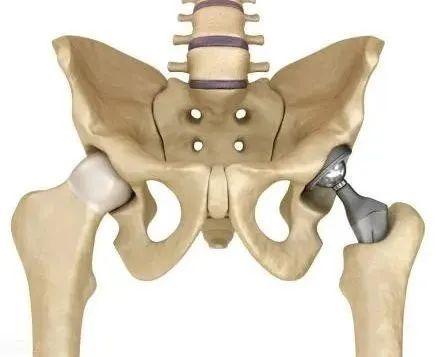

股骨头是髋关节的重要组成部分

在盆骨下方

大腿根部

起着承上启下的作用